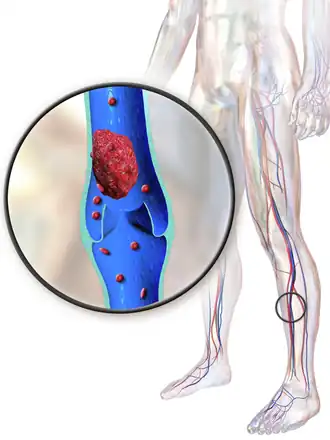

Trombose venosa profunda (TVP) é a formação de um coágulo sanguíneo numa veia profunda, geralmente nas pernas.[1][a] Os sintomas incluem dor, inchaço, vermelhidão ou sensação de calor na área afetada.[1] Entre as possíveis complicações estão embolia pulmonar, como resultado de um coágulo que se desprende e se fixa nos pulmões, e síndrome pós-trombótica.[1][2]

Os sinais e sintomas mais típicos são dor ou sensibilidade, inchaço, calor, vermelhidão ou descoloração e distensão das veias da superfície do local afetado, embora cerca de metade das pessoas com a condição não tenha sintomas. Geralmente afeta uma das pernas após repouso prolongado.[6]